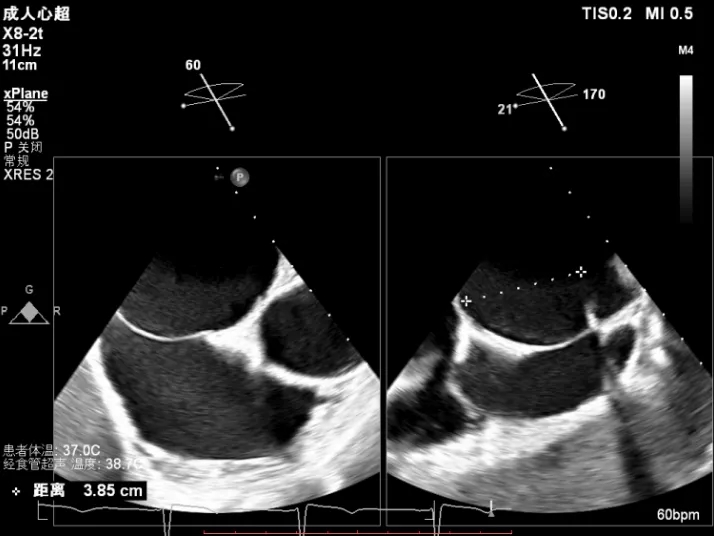

术前X-Plane

全麻下穿刺右股静脉,在TEE指导下完成房间隔穿刺,穿刺处与二尖瓣瓣环距离3.85cm。将superstiff导丝送至左房,应用18F鞘管扩张穿刺部位,沿导丝将可操控导引导管送入左肺静脉。